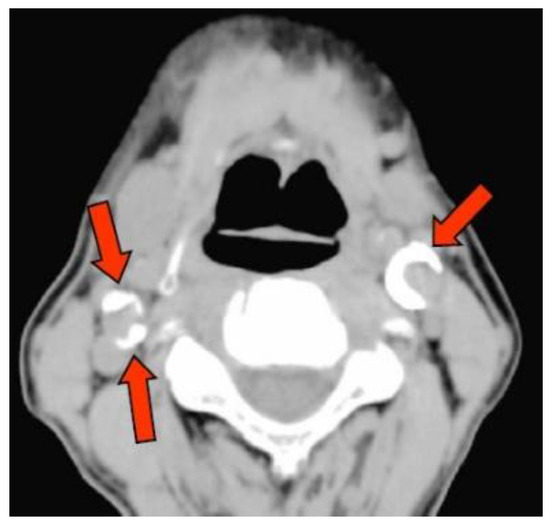

2.3. Detection of CAC on CT